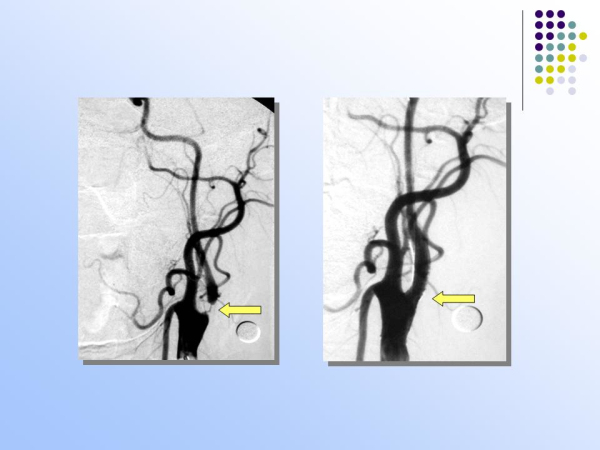

【治疗脑血管病的新技术:血管内介入治疗】—神经内科脑卒中筛查与防治办公室

脑卒中筛查与防治办公室